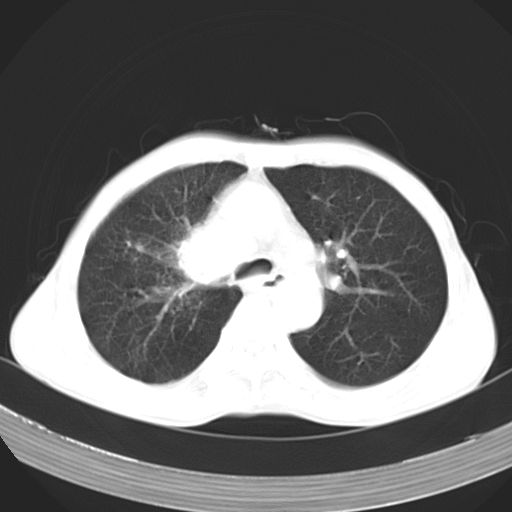

以下是引用苯小孩在2007-5-24 12:47:00的发言:[br]右侧肺门处不均匀密度软组织块影,远端肺组织见斑片模糊影,纵隔内淋巴结明显肿大,边界不清.<纵隔窗第12层面支气管内似见软组织结节>[br]考虑:1、右侧中央性肺癌并阻塞性肺炎并纵隔淋巴结转移可能性大.建议强化或纤支镜进一步检查.[br]2、隆突下淋巴结肿大/食道病变?请做鉴别检查.

以下是引用zhangzhongshou在2007-5-24 12:55:00的发言:[br]1、右肺中叶中心型肺癌并右肺门、隆突下、纵隔淋巴结转移。右肺中叶阻塞性肺炎。

以下是引用jw-830在2007-5-24 15:24:00的发言:[br][br] [br] 考虑右肺中央型肺癌并阻塞性炎症,右肺门及纵隔淋巴结转移。 [br] [br][br]